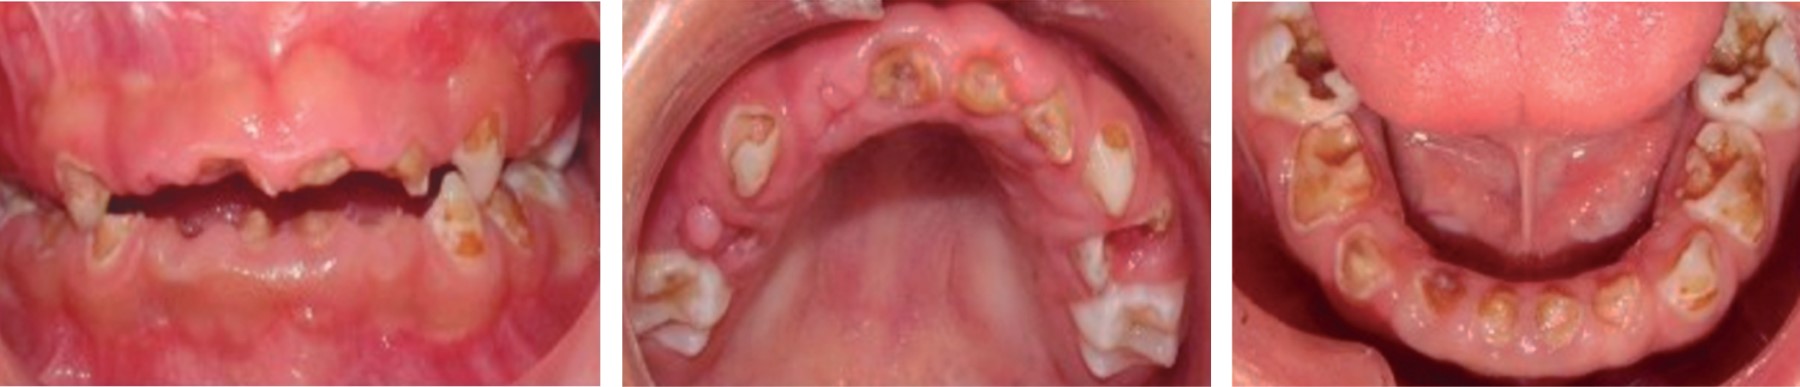

Durante la exploración física y el examen intraoral del paciente se observó higiene bucal deficiente, con lesiones cariosas de segundo, tercer y cuarto grado, diagnosticado con caries de la infancia temprana severa y gingivitis generalizada (Tabla 2). El paciente en el momento del examen oral presentaba dentición temporal, paladar profundo oval, lengua saburral, frenillos bien implantados a excepción del frenillo lingual, el cual se observó corto (Figura 2).

Figura 2